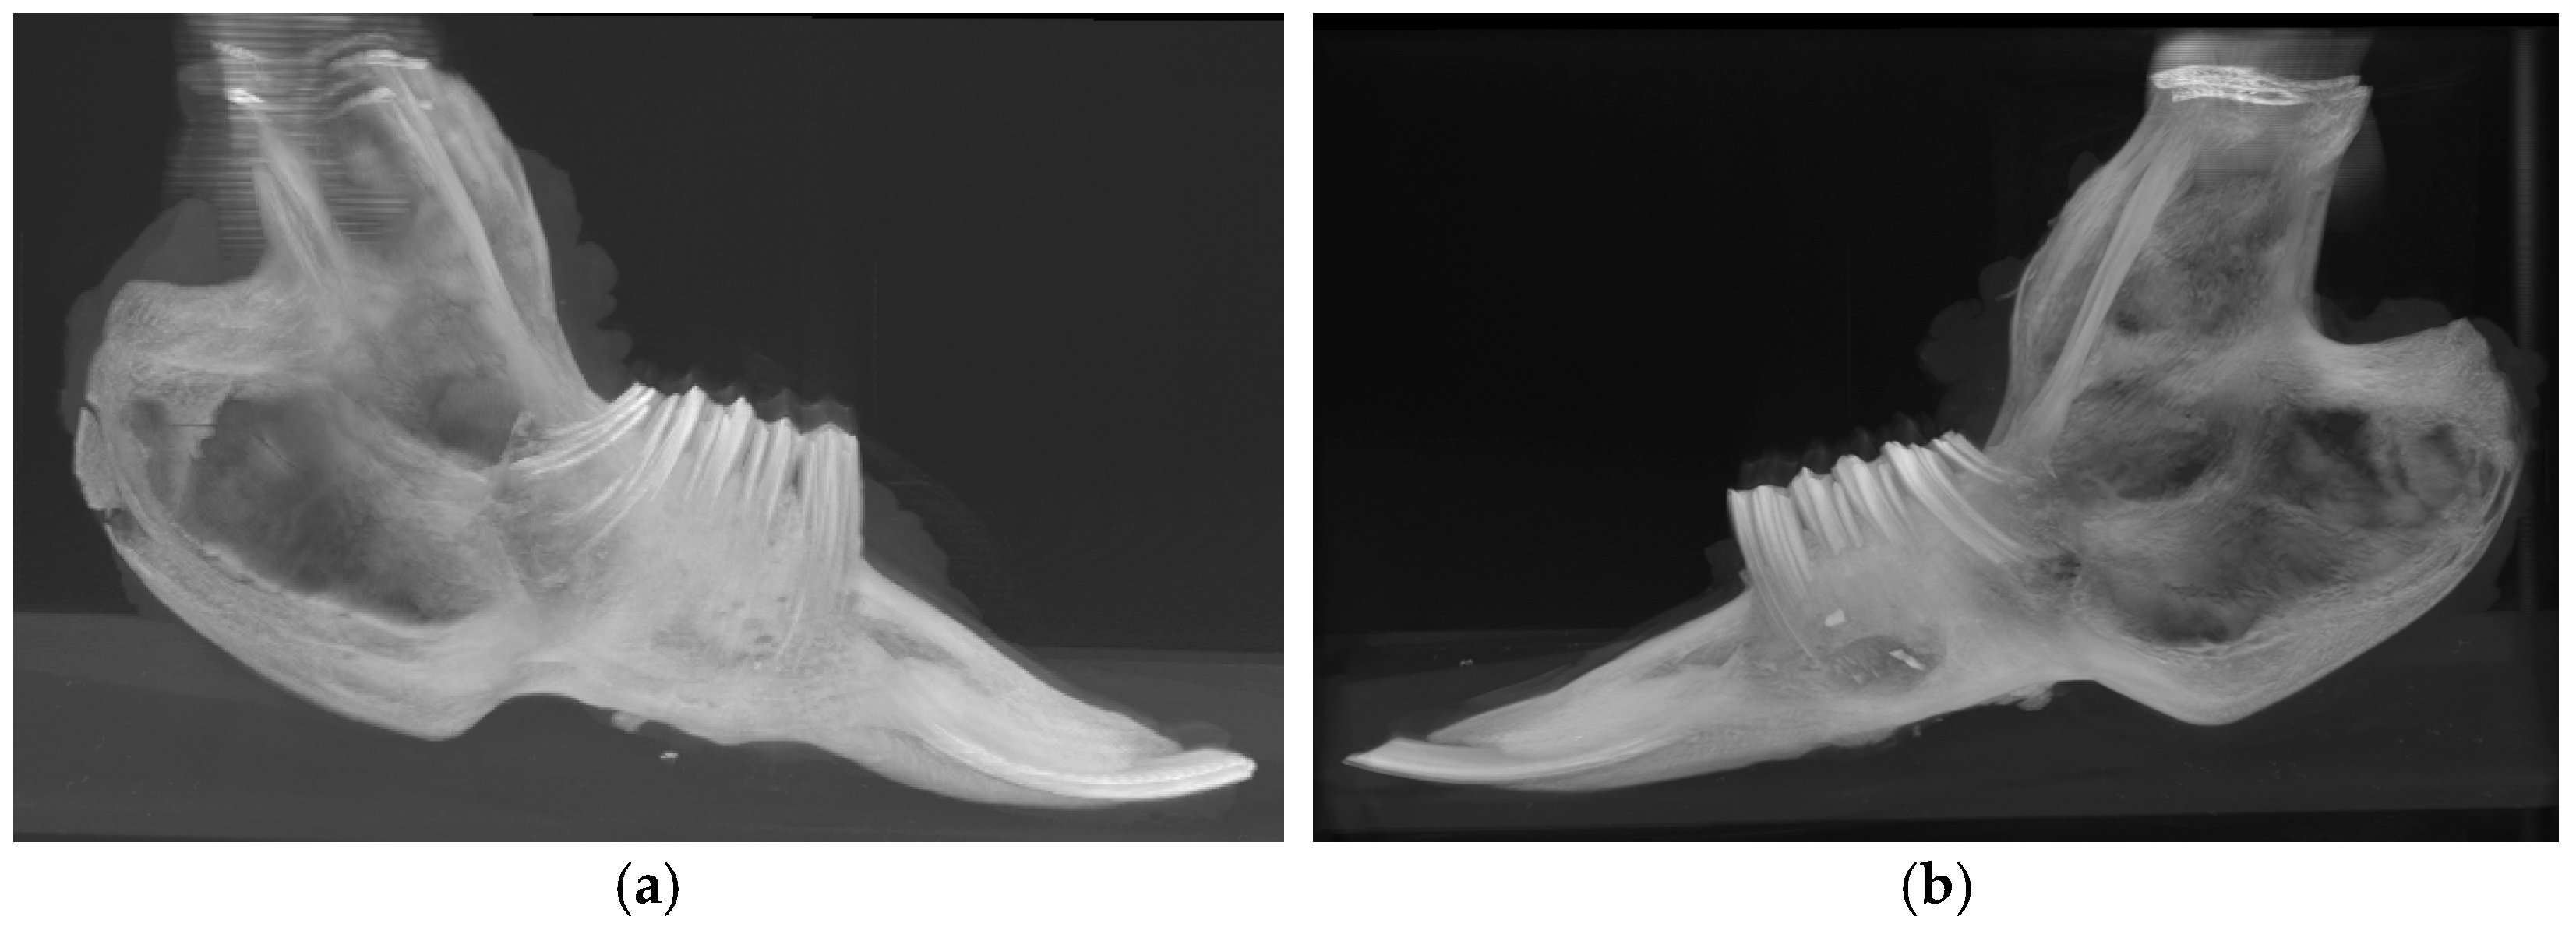

2.5. Computed Tomography (CT) and Micro-CT Analyses (μCT)

3.3. Radiological and Micro-CT Analyses (μCT)